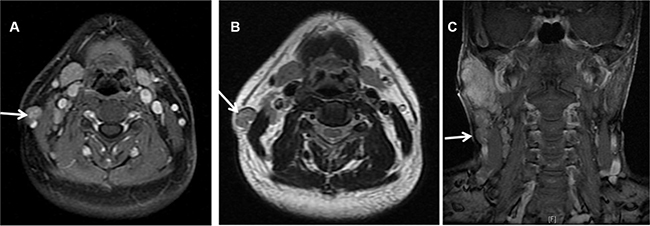

Figure 2: MRI showing nodal metastasis (arrow) at the surface of the right sternocleidomastoid muscle in a 51 years old male patients with LELC of the right parotid. (A) Contrast enhanced transverse T1WI MRI with fat suppression. (B) Transverse T2WI MRI. (C) Contrast enhanced coronal T1WI MRI with fat suppression.

There were 5 patients with nodal metastasis located between the lateral border of the sternocleidomastoid muscle and the platysma (Figure 2), much lower to the parotid gland, but lateral to level II node. From the anatomic point of view, they did not belong to any of the levels classified in the 2013 updated consensus guidelines. These 5 patients had multiple nodal involvements at the ipsilateral neck.